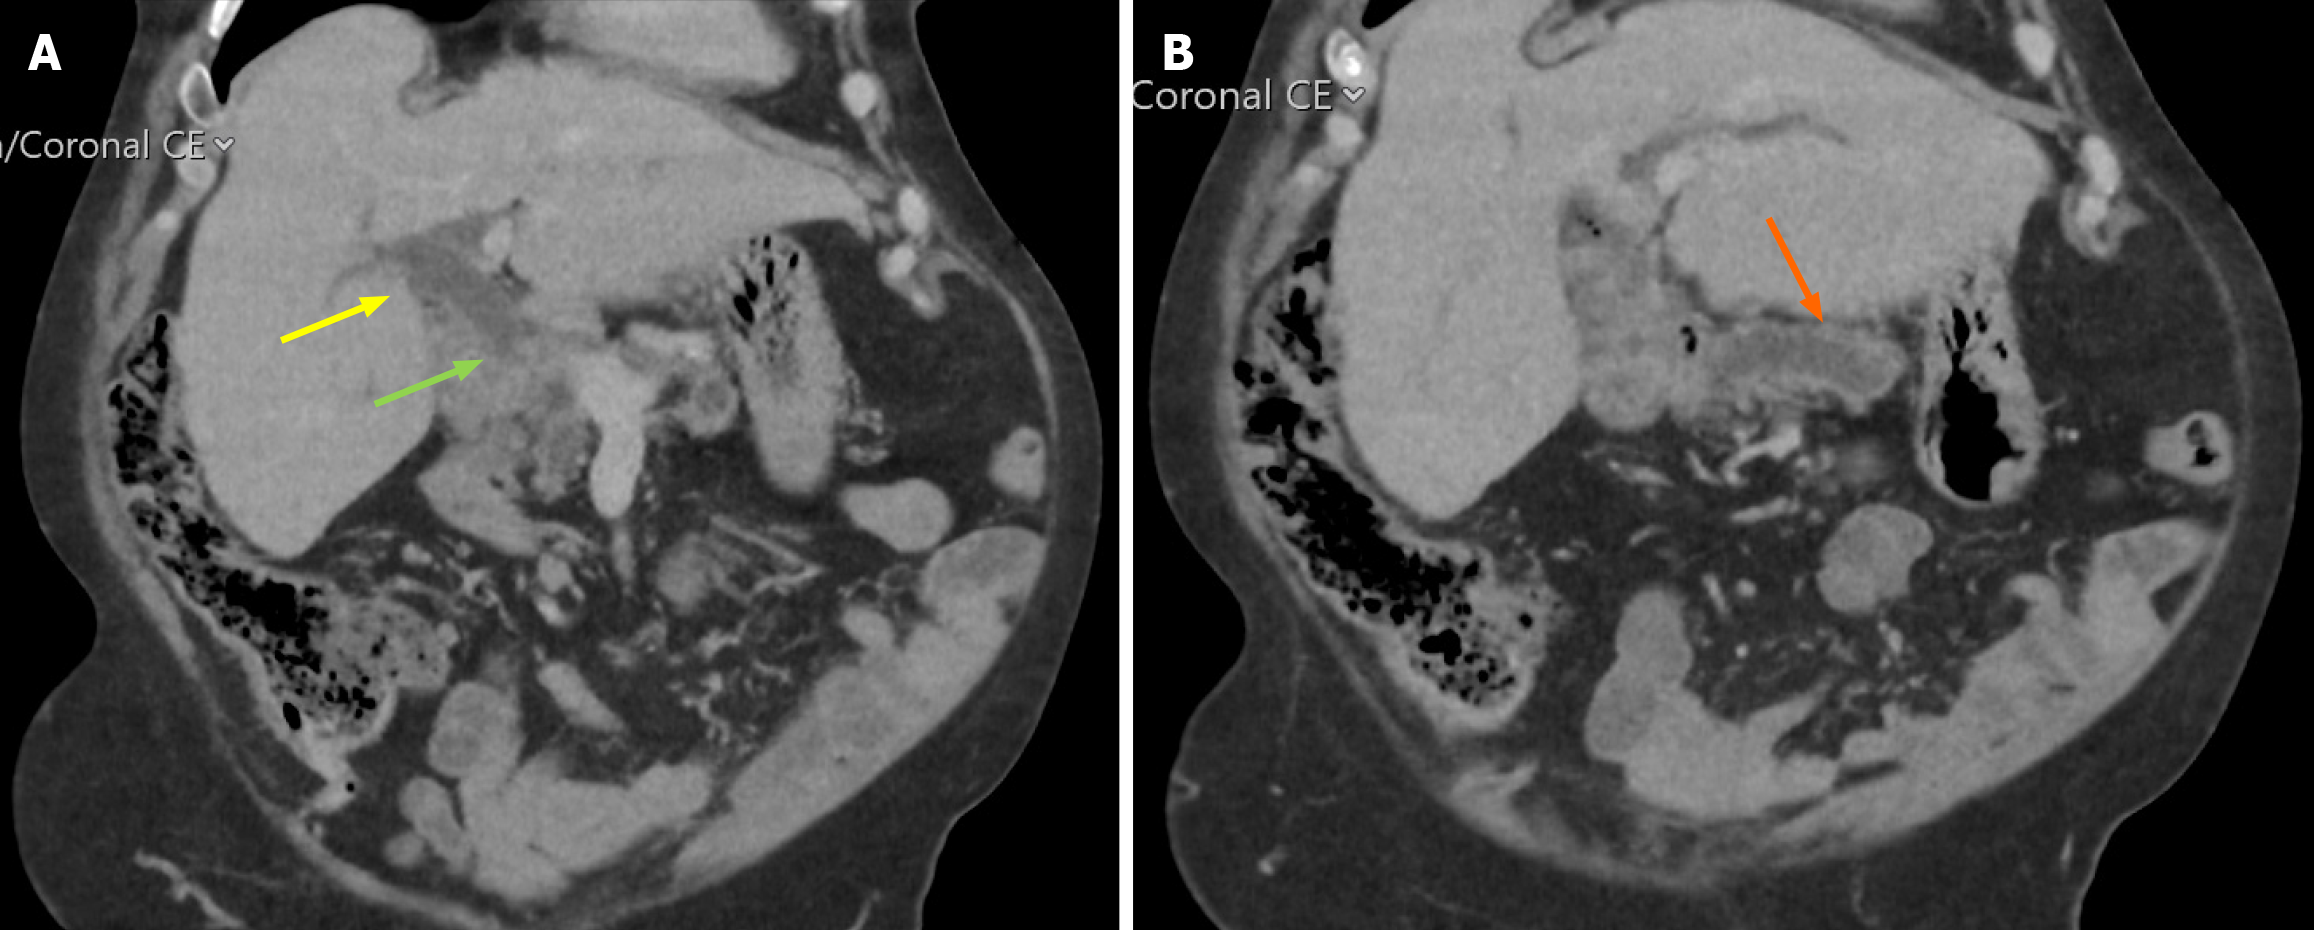

Contrast-enhanced computed tomography demonstrated dilated pancreatic duct measuring 9 mm with associated pancreatic parenchymal atrophy (Figure 1). Endoscopic visualisation of the ampullary lesion during ERCP was limited due to luminal collapse; a biliary stent was inserted. Positron emission tomography revealed no evidence of distant metastatic disease (Figure 2).